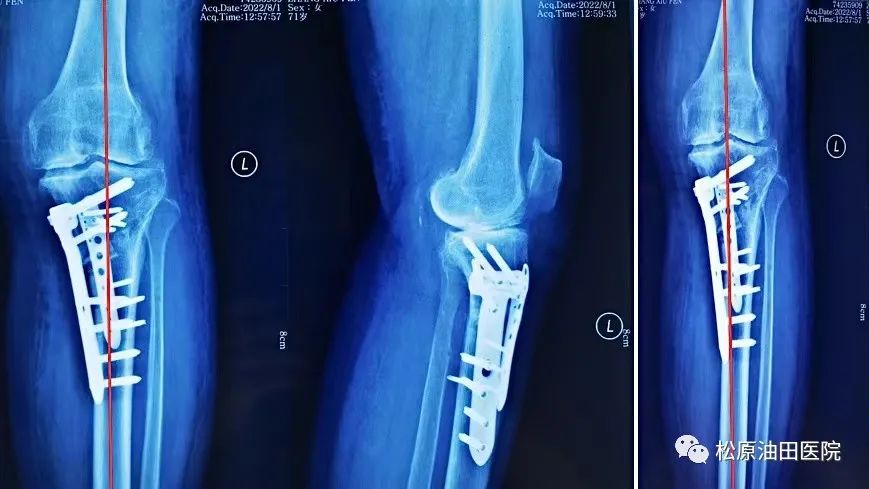

据悉,今年松原吉林油田医院放射线科引进开展负重位下肢全长的影像系统检查项目,它可以全面观察骨与关节的形态、密度的改变,负重位真实对生理角度、畸形角度、力线进行测量,为下肢畸形矫正、植骨术,尤其是膝关节矫形术或关节置换术前、术后提供了有力的测量依据。在此基础上,医院骨三科主任冯宪发团队在松原率先开展了不换膝关节“微创保膝”治疗新技术,此技术为国内领先技术,达到了推迟或不换膝关节治疗膝关节骨性关节炎。